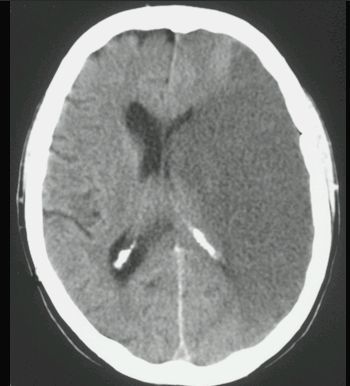

UDAR NIEDOKRWIENNY MÓZGU (ZAWAŁ MÓZGU)

TK